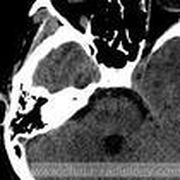

脑动脉瘤是颅内动脉血管的异常瘤状突起。脑动脉瘤不破裂,一般病人没有明显症状,如果破裂出血,常表现为蛛网膜下腔出血,病人可以出现剧烈的头痛,恶心呕吐,甚至出现...11216人收听

脑动脉瘤是什么引起的